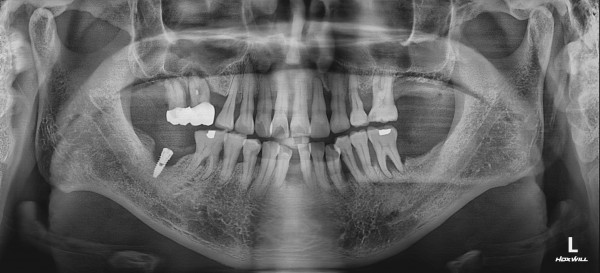

CASE 01 최고관리자 0건 25-01-06 11:57 본문 상악동거상술 임플란트 목록 이전글CASE 01 25.01.06 다음글CASE 02 25.01.06 댓글목록 0 댓글목록 등록된 댓글이 없습니다.